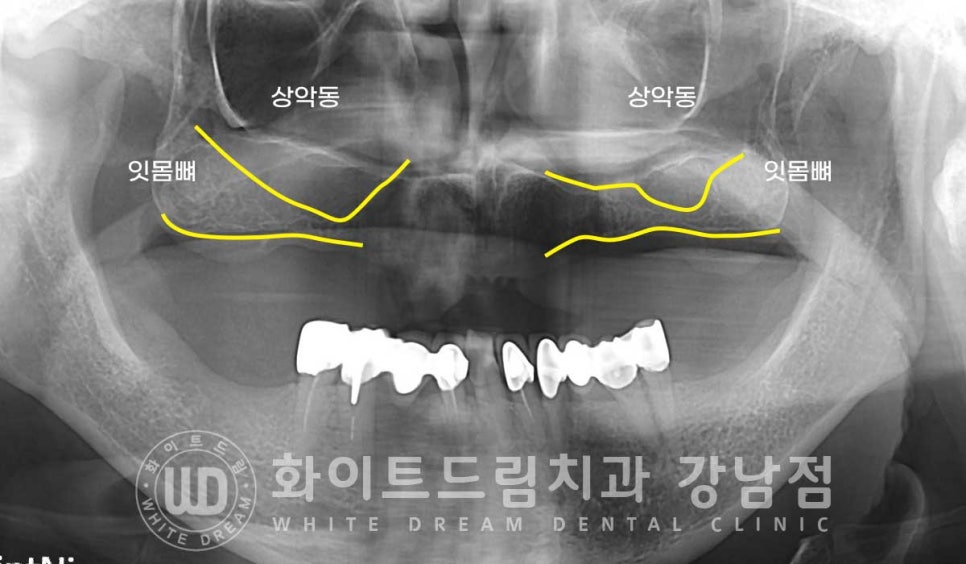

하악은 치아가 남아있는 상태이나, 상악 치아가 하나도 없으신 상태입니다.

특히 이전에 치아를 발치하게 된 이유가 '심각한 염증이지 않았을까'

라고 예상이 될 만큼 심한 잇몸뼈 소실을 보이는 상태였습니다.

구내 상악 사진을 보면 움푹 들어간 부분이 육안으로도 쉽게 확인될 정도로

골 소실이 심한 상태입니다.

이 상악 부위는 많은 양의 뼈이식이 필요할 것으로 예상되어

상악동 거상술식 중에서도 lateral, 측방 접근법을 이용하여

상악동을 크게 거상시킨 후 뼈이식을 진행해야 할 것으로 보였습니다.